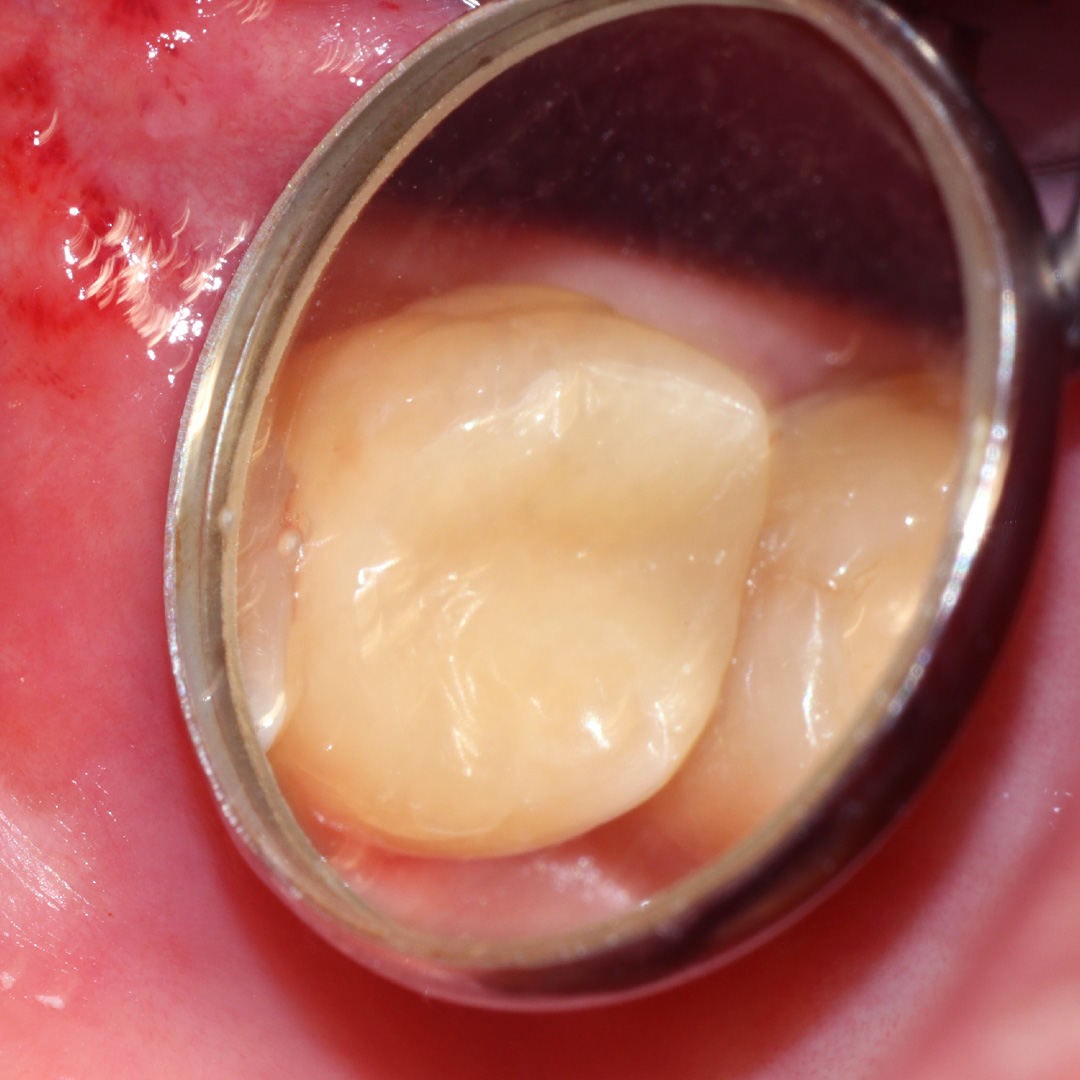

До и после лечения

В клинику «Стоматология Комфорта» обратился пациент с жалобой на выпадение пломбы из моляра верхней челюсти, а также на чувствительность зуба к перепадам температуры и застревание кусочков пищи. В результате осмотра выявлен хронический глубокий кариес зуба 27. Проведено лечение с применением светоотверждаемого композита Эстелайт.

- установка пломбы из светоотверждаемого композита Эстелайт;

- шлифовка и полировка зуба.